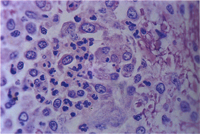

肉眼病變: 局部性慢性炎症見於整個腦組織,主要侵犯血管周圍形成很厚的非化膿性炎症細胞增生(圖1),包括淋巴球、組織球、類上皮細胞、吞噬細胞與少許漿細胞,偶爾亦有嗜中性球(圖2)。炎症細胞圍繞血管厚薄不一,圍繞不均勻,有時較集中於血管一端而呈偏心。又各種炎症細胞出現增生程度不均,有的圍繞為清一色淋巴球(圖3),有的則大部分為組織球或吞噬細胞(圖4)。特殊染色如PAS並無特殊發現,本病例又可看到一些血管變性(degenerated vessels)。病變發生於腦脊髓與腦膜,灰白質均可被侵犯,炎症細胞增生,侵犯非只限於血管周圍,亦可侵入腦實質neuropil。